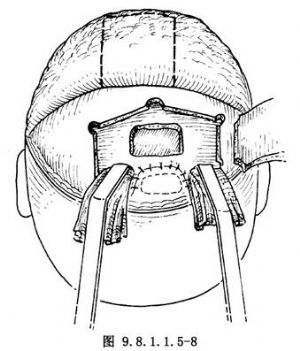

(1)顱腔術區關閉:清潔沖洗顱內術區,確實封閉硬腦膜裂口和缺損。製作額部腱膜瓣,蒂留於下方(圖9.8.1.1.5-8),由骨窗下緣轉入顱內,並於蝶骨平板和雙側眶板切緣處鑽孔縫合(圖9.8.1.1.5-9)。去除顱內敷料,大腦額葉復位,額骨瓣復位,鋼絲固定。復位額顳組織瓣,分層縫合(圖9.8.1.1.5-10)。前顱底缺損區,除硬腦膜修復外,又轉入了較厚的額部腱膜瓣,故骨缺損較小時可不作硬組織修復,但骨缺損區過大,則應用骨組織修復。